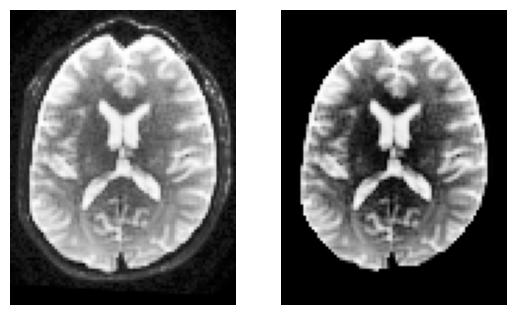

To keep things simple, we’ll compute a brain mask using median_otsu.

This function is inspired from Mrtrix’s bet which has default values median_radius=3, numpass=2. However, from tests on multiple 1.5T and 3T data from GE, Philips, Siemens, the most robust choice is median_radius=4, numpass=4 (default)

sli = data.shape[2] // 2

plt.subplot(1, 2, 1).set_axis_off()

plt.imshow(histeq(data[:, :, sli,0].astype("float")).T, cmap="gray", origin="lower")

plt.subplot(1, 2, 2).set_axis_off()

plt.imshow(histeq(b0_masked[:, :, sli,0].astype("float")).T, cmap="gray", origin="lower")